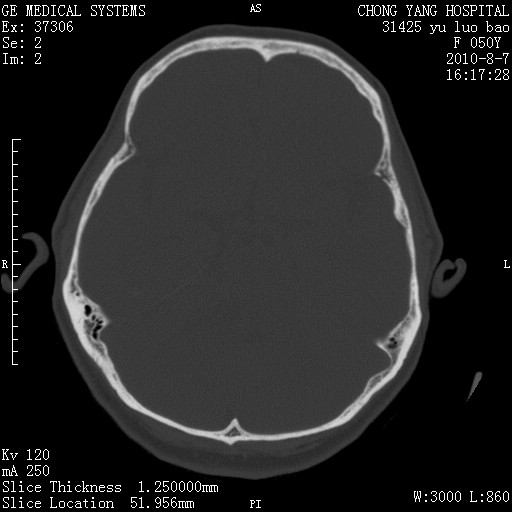

骨窗示右侧内听道扩大,考虑右侧听神经瘤。